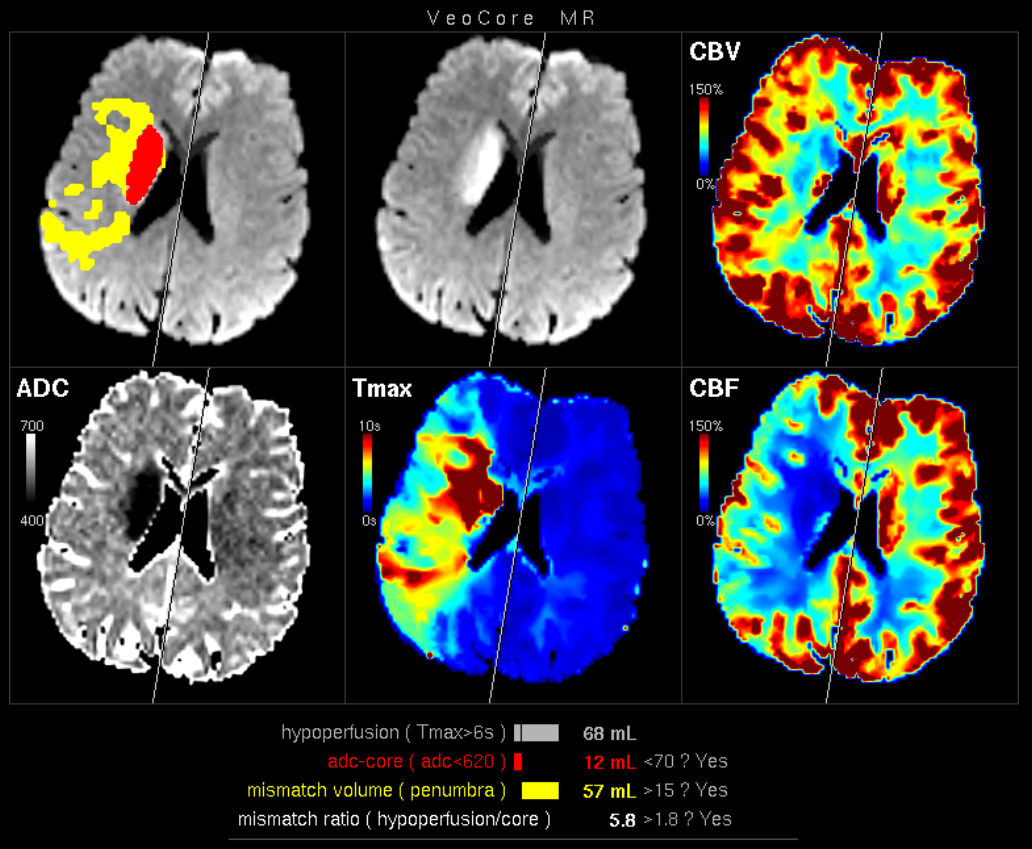

Des Weiteren ist mRay in der Lage eine Verarbeitung von Bildern durchzuführen und so Veränderungen bzw. Anomalien in Geweben zu finden, zu visualisieren und zu quantifizieren. Das Bildverarbeitungsmodul mRay VEOcore kann verwendet werden, um Bilder des Gehirns von Bildgebungsmodalitäten wie CT, Perfusions-CT oder MRT mit diffusionsgewichteter Auswertung (DWI) zu prozessieren. Als Ergebnis werden Kontrastveränderungen über die Zeit als farbige Perfusionskarten angezeigt, dies beinhaltet auch flussbasierte Parameter und Gewebeblutvolumen Berechnungen.

Die Perfusionsanalyse von Aufnahmen des Gehirns ermöglicht die Darstellung und Quantifizierung von minderdurchblutetem Gewebe (Penumbra), nicht-durchblutetem Gewebe (Kerngewebe) und dem Mismatch-Ratio zwischen den beiden Werten. Die berechneten Werte können der Unterstützung bei einer Entscheidungsfindung dienen, die auf der Beurteilung des Ausmaßes der Schädigung von Geweben basiert.